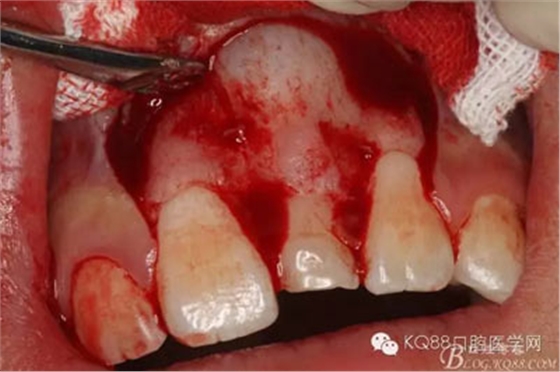

圖9.超聲骨刀去除隆起的骨壁

圖10.形成梯形骨縫

圖11.掀開骨壁。摘除牙瘤及牙囊組織